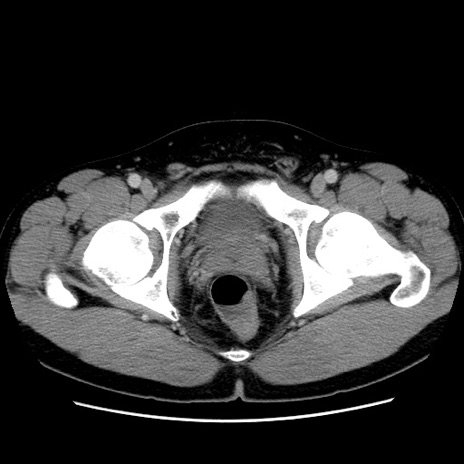

症例4(横断像)

【症例】30歳代男性

【主訴】腹痛、嘔吐

【現病歴】昨晩から突然の腹痛あり、その後嘔吐、軟便も出現。腹痛が改善しないため救急搬送となる。2日前にしめ鯖の食事歴あり。

【身体所見】意識清明、苦悶様、BP 135/90mmHg、BT 35.7℃、腹部:平坦、やや硬、心窩部〜臍部に自発痛、圧痛あり、筋性防御+、反跳痛-

【データ】WBC 8100、CRP 0.57